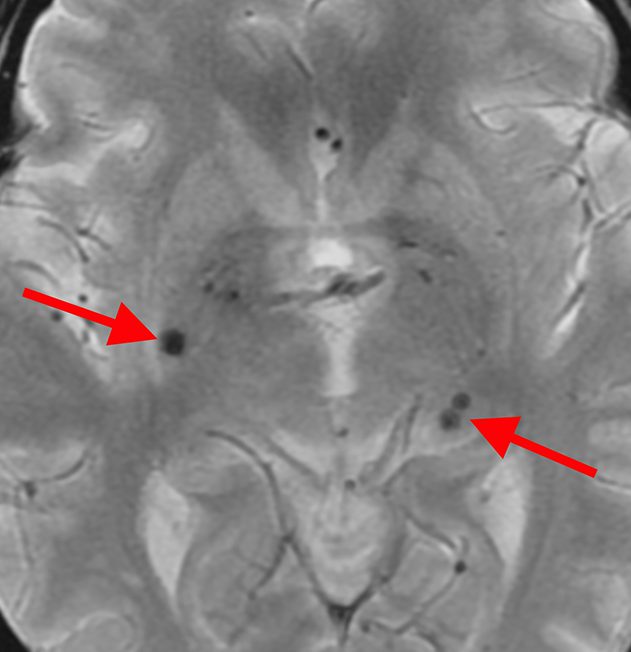

微小脳出血

これらの状態はいずれも無症状です。悪化した場合、後遺症が残る可能性もあるため、高血圧症や糖尿病のコントロールが必要です。